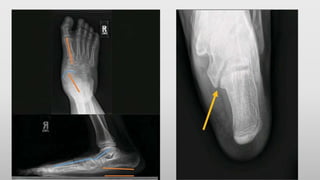

•Radiography- Ap,lateral

45 degrees internal

oblique view,

harris beath view

•CT scan , MRI

• Calcanealnavicular coalition – anteater

nose sign

Talocalcaneal coalition- C sign , talar beaking